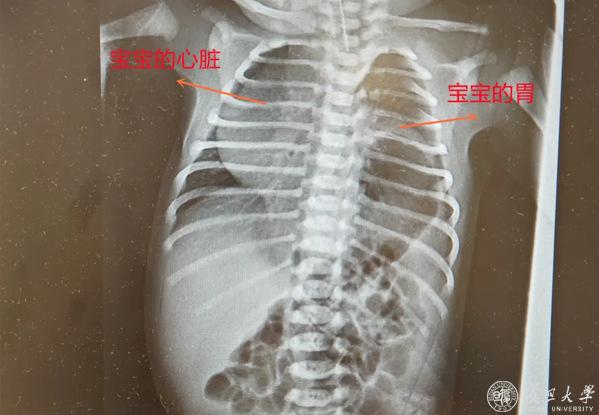

30岁的J女士在大排畸时,被告知胎儿或患左侧膈疝,心脏、胃等器官“错位”,恐致严重肺发育不良、肺动脉高压,甚至胎死宫内,她与家人陷入焦虑。

危急时刻,J女士求助妇产科医院。医院迅速启动多学科协作机制,由主任医师张斌牵头,联合产科、新生儿科、超声科专家,并特邀儿科医院专家会诊。评估后判定胎儿为中危膈疝,羊水正常,若孕期维持肺部发育稳定,足月分娩后经特殊处理与手术,孩子有正常成长机会,这让J女士一家重拾信心。

此后孕期,每次产检都是“闯关”。孕26周至38周,医院为J女士安排高频次高危超声监测,追踪胎儿O/ELHR(评估肺部发育关键指标)及胸腔积液情况。幸运的是,多次检查显示胎儿无水肿、无心包积液,肺头比持续≥45%,器官发育良好,为后续诊疗奠定基础。

孕38周,J女士突发宫缩,产科副主任医师沈婕团队立即启动应急预案,顺利实施剖宫产。同时,新生儿科团队开展子宫外产时处理(EXIT),在胎儿未脱离母体、靠胎盘供血时快速完成气管插管,保障宝宝出生后能自主呼吸。随后,儿科医院儿外科团队接力实施膈疝修补术。经多学科团队无缝协作与照料,宝宝术后恢复顺利,平安出院。这场跨越数月的生命守护,最终以圆满结局落下帷幕。